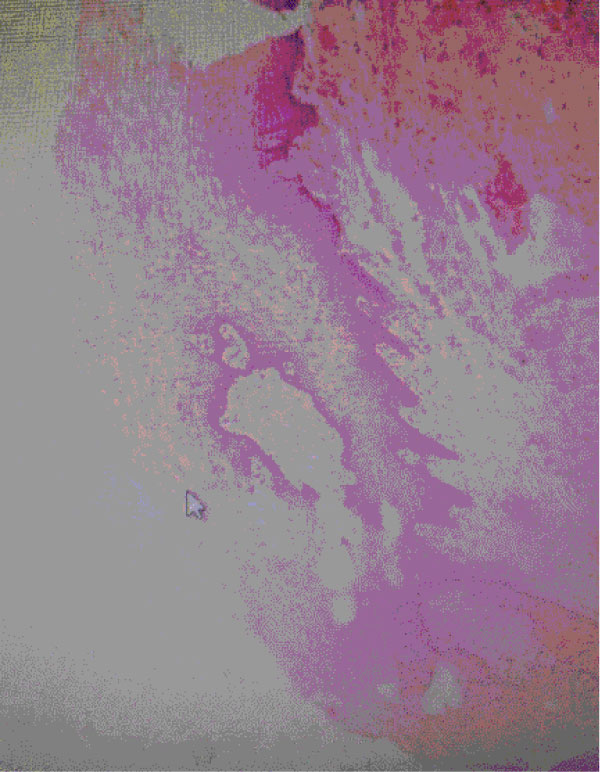

The analysis of the vaginal tissue samples collected at T0 showed signs of atrophic vulvo-vaginitis at different stages, but all samples presented a remarkable thinning of vulvo-vaginal epithelium, a reduction or disappearance of papillae and a marked fibrosis of chorion. In addition, a significant reduction in collagen activity was observed accompanied by an increase of inflammatory infiltrate, predominantly lymphocytic, and in few cases the typical lichenoid "band" arrangement could be seen Figure 1.

Figure 1: Vaginal sample at T0: Vaginal Histology at baseline. View Figure 1